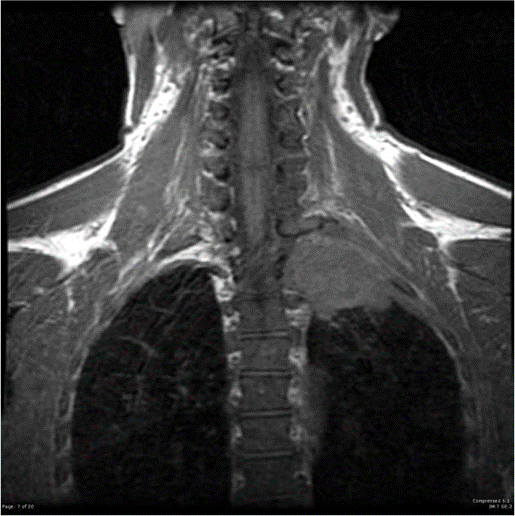

List the possible structures that may be possibly involved in Pancoast tumor.

Why would you get Horner Syndrome secondary to a lung tumor?

Features of Horner Syndrome?

Involvement of sympathetic ganglia

Ptosis, miosis, anhydrosis, enophthalmos, loss of cilisospinal reflex